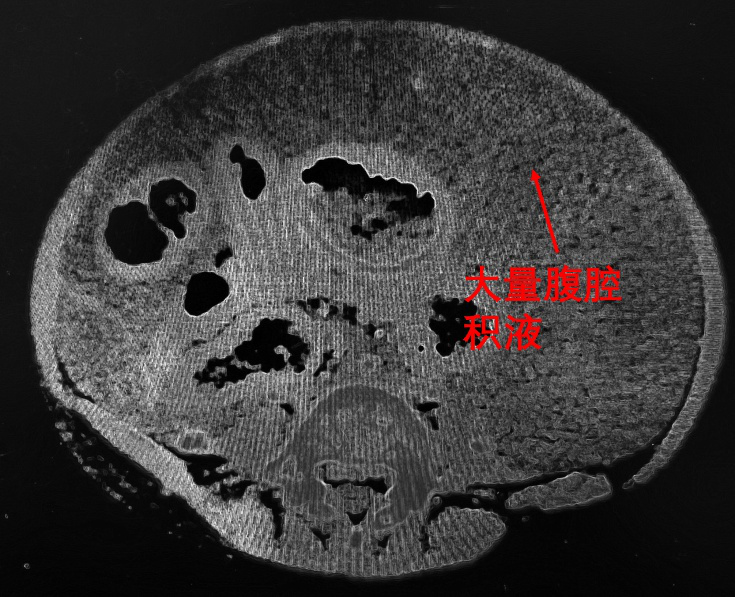

图2.患儿术前CT。肝右静脉闭塞,肝后性门静脉高压。门静脉支架重度狭窄,肝前性门静脉高压。两项门静脉高压同时存在,导致肠系膜上静脉回流肝脏受阻,肠表面渗出大量腹腔积液。

图3.术前CT,患儿大量腹腔积液